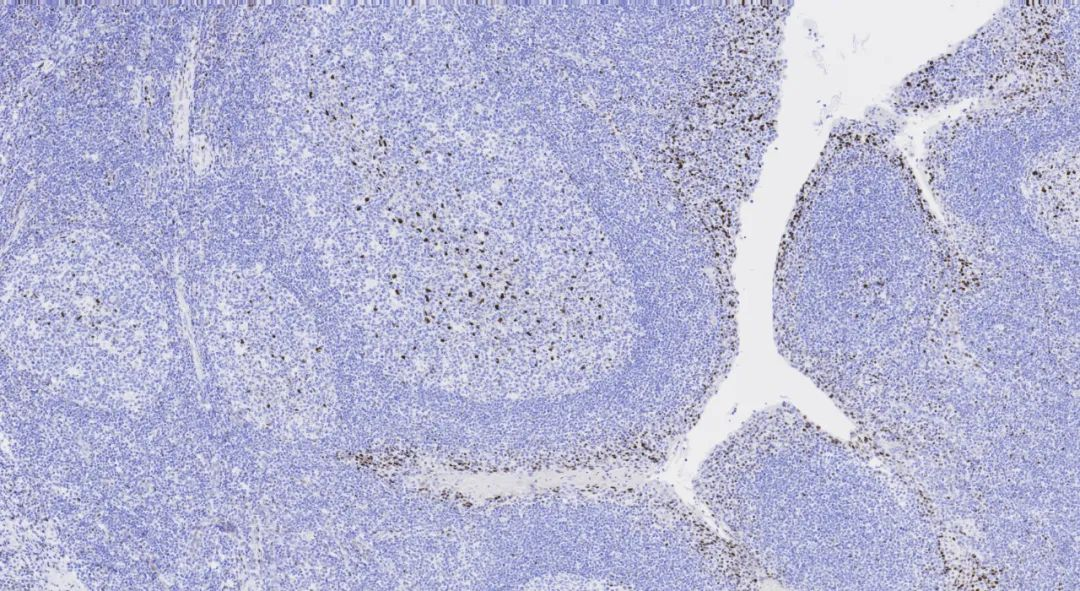

390 laboratories participated, with a pass rate of 70% (excellent rateSynaptophysin is mainly present in the presynaptic vesicle membranes of neurons, expressed in adrenal medullary cells, pancreatic islet cells, thyroid parafollicular C cells, parathyroid chief cells, skin, anterior pituitary cells, and neuroendocrine cells. It is primarily used for the diagnosis and differential diagnosis of pheochromocytoma, ganglioneuroma, paraganglioma, and tumors of the APUD system.

SYP, with a total ofNeuroendocrine tumorSYP (MX038) staining imageFigure 4.Figure 5.the seventh assessment by NordiQC forColon47%)。